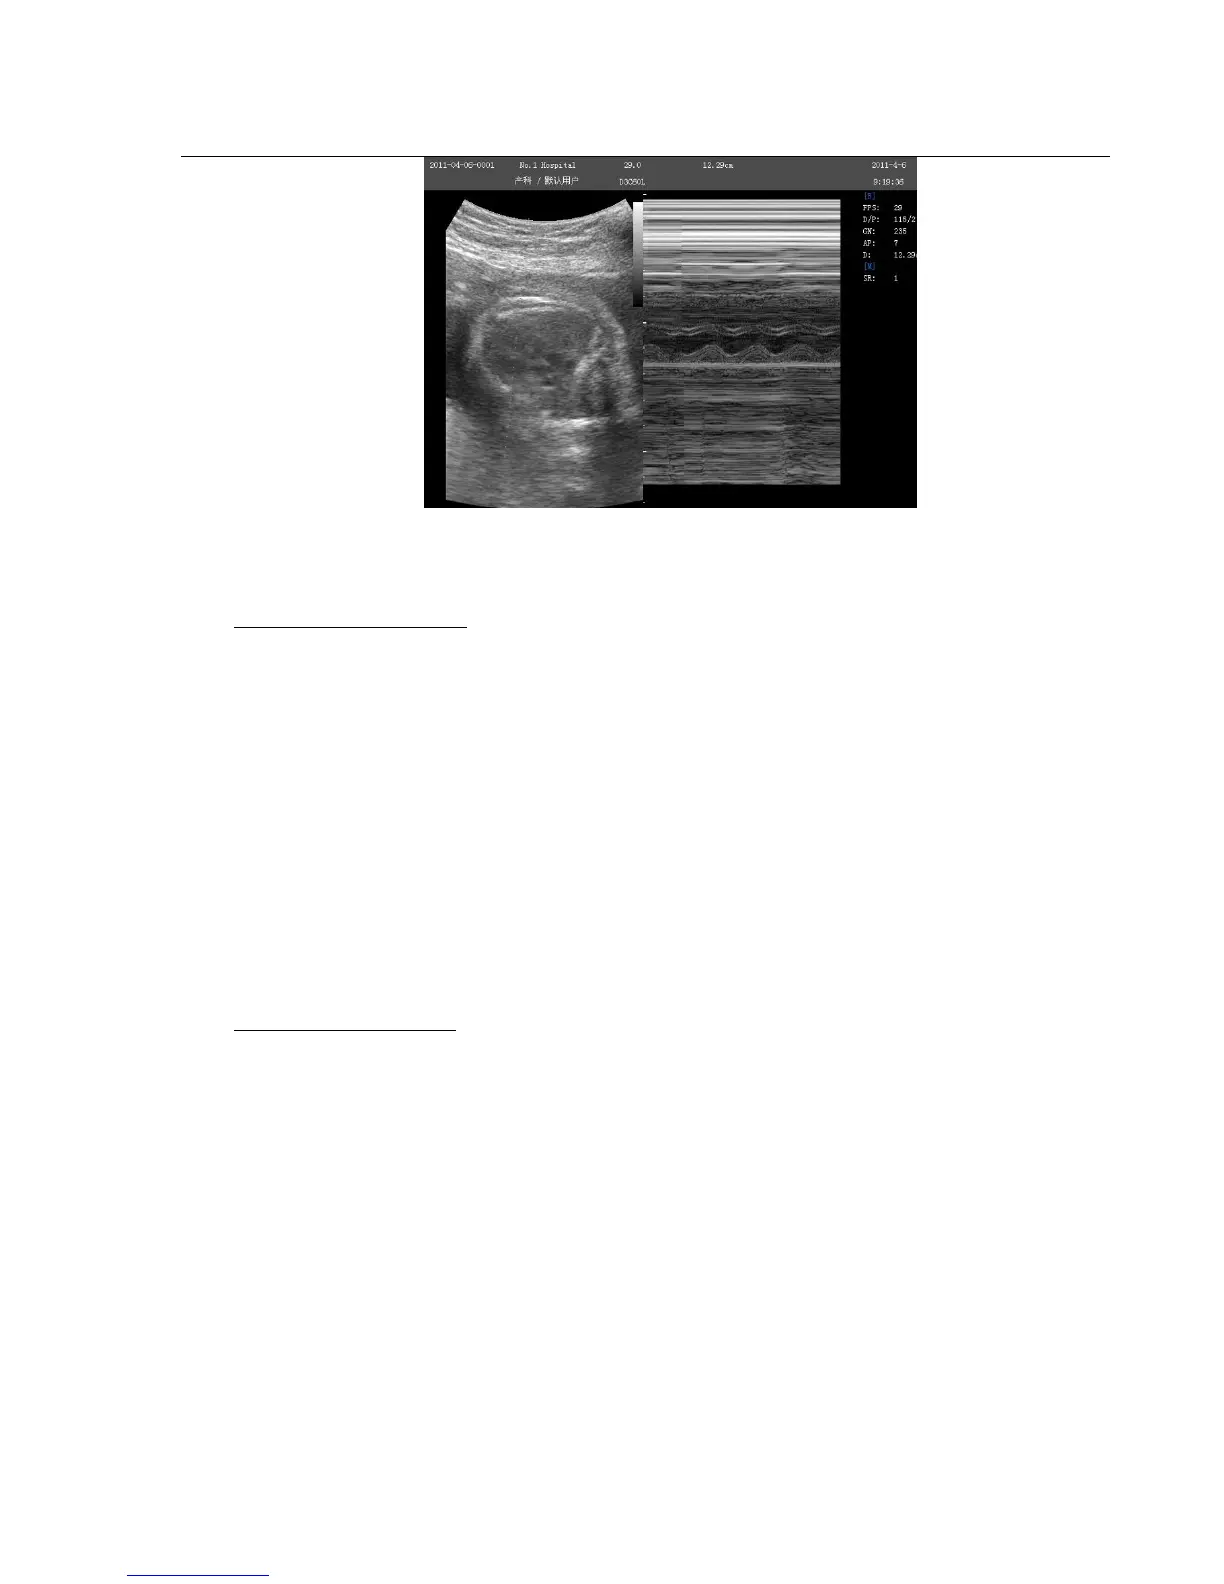

Fig. 4-8 B/M Mode

M-mode Exam Procedure:

Get a good B-mode image. Survey the anatomy and place the area of interest near the center of the B-mode

image.

Press the M-knob, move the Trackball to position the M cursor over the area that you want to display in M-

mode.

Adjust the Sweep Speed, TGC, Gain etc, as needed.

Press the FREEZE-key to stop the M scanning.

Record the image to hard disk or to the printer (hard copy device).

Press FREEZE-key to continue imaging.

Press M-knob to enter into M-mode.

Press M –knob again to exit M-mode.